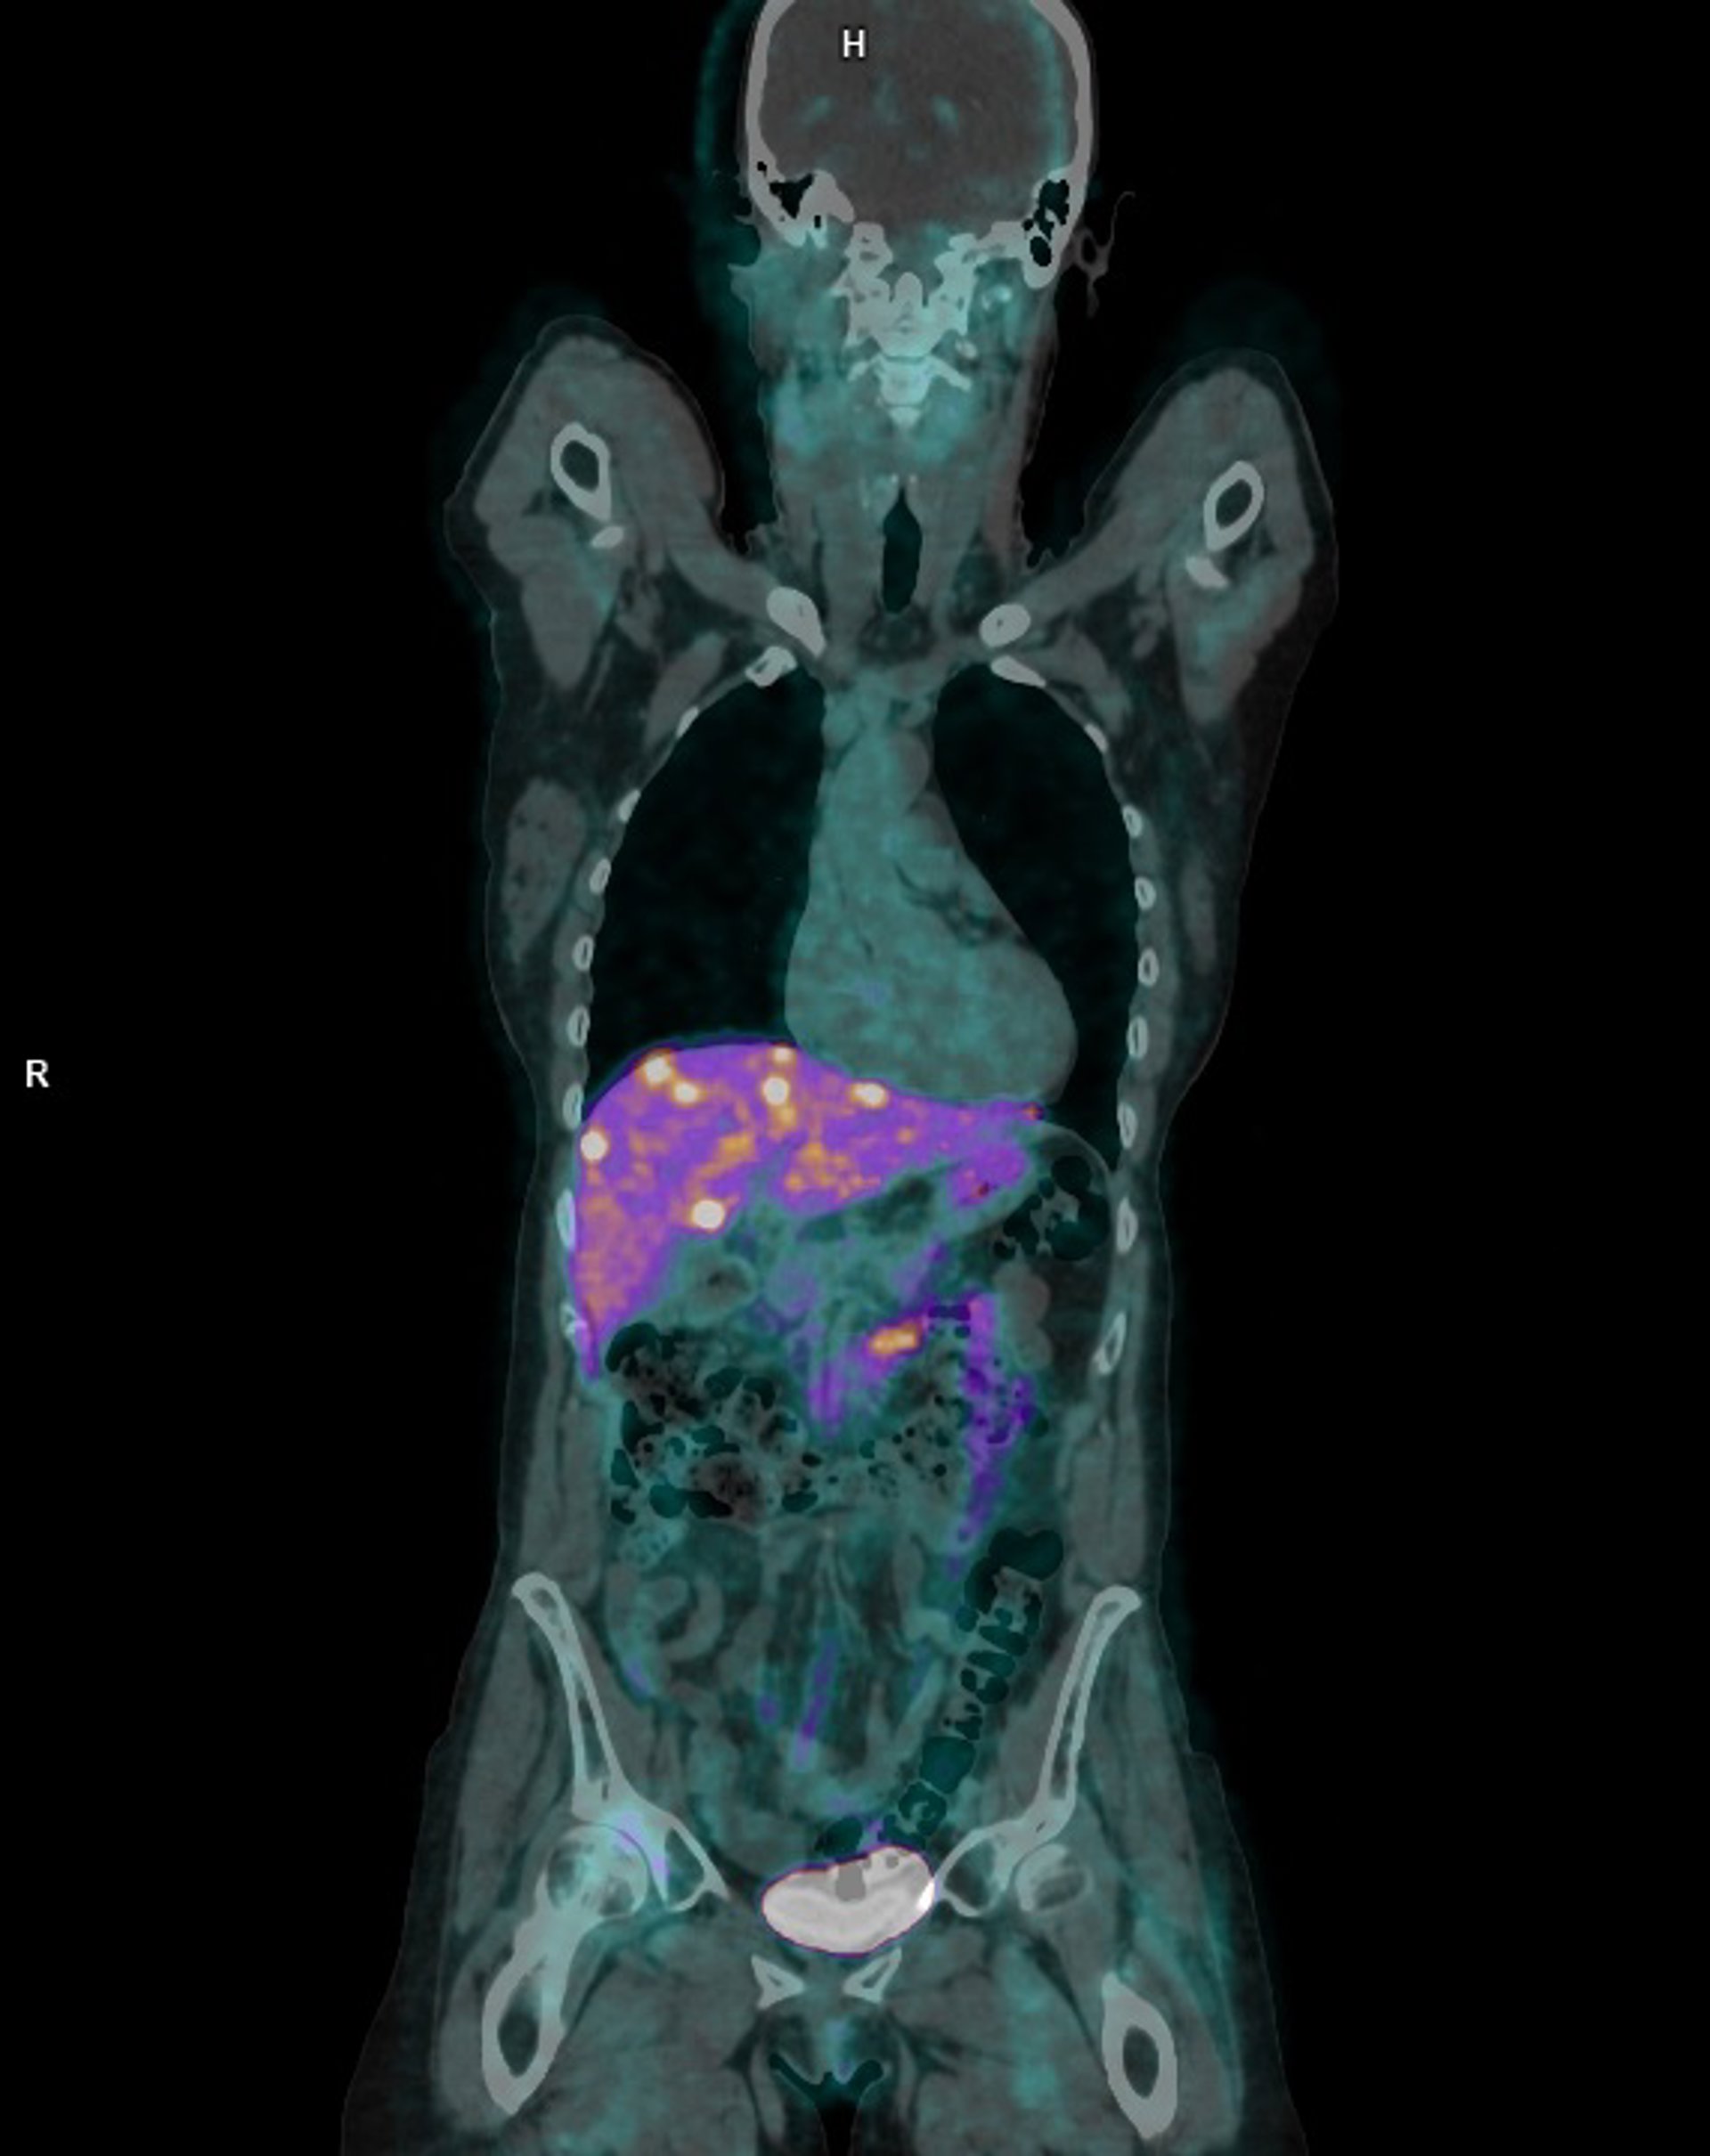

Una de las pruebas realizadas con el nuevo radiofármaco.

Una de las pruebas realizadas con el nuevo radiofármaco. - JUNTA DE ANDALUCÍA

El Hospital Universitario Reina Sofía de Córdoba ha realizado con éxito el primer estudio en Europa utilizando cobre-64 (64-Cu) Dotatate, un radiofármaco de última generación para el diagnóstico de tumores neuroendocrinos. Concretamente, este trazador se utiliza en el PET-TAC para la localización de tumores que son positivos para el receptor de somatostatina, permitiendo su visualización mediante la exploración.

En un comunicado, el jefe de servicio de Medicina Nuclear, Juan Antonio Vallejo, ha explicado que el 64-Cu "ofrece mayor calidad de imagen, mejor contraste de las lesiones y una ventana temporal más amplia para la logística de suministro y para la obtención de imágenes, lo que facilita una estadificación más precisa y una planificación terapéutica individualizada".